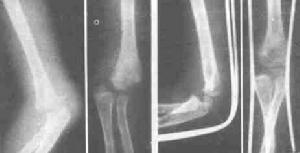

肱骨外髁骨折x片X線照片顯示肱骨小頭的骨折線多超過化骨核的1/2,或不通過小頭化骨核,而通過肱骨小頭與滑車間溝的軟骨在乾骺端處有一骨折線。骨折塊可向外側移位。骨折脫位型X線片,正位片顯示骨折塊連同尺橈骨可向橈側或尺側移位,側位片顯示可向後側移位,偶可見向前移位者。肱骨外髁骨折在X線片上表現為多種多樣,在同一骨折類型中表現也常不一。

Ⅰ型:無移位骨折型。骨膜未撕裂,X線片可見到乾骺端有骨折線。

Ⅱ型:側方移位型。骨塊向側方、前方或後方移位。骨折端間隙增大輕度移位者,骨膜部分撕裂,重度移位者,完全撕裂,復位後骨塊不穩定,在固定中可發生再移位。

Ⅲ型:鏇轉移位型。骨折塊向側方、前方或後方移位。並鏇轉移位。由於局部伸筋膜骨膜完全斷裂,加之前臂伸肌的牽拉,故骨折塊縱軸向外鏇轉移位可達90°-180°。在橫軸上也可發生向前或向後的不同程度的鏇轉。肱尺關節無變化。